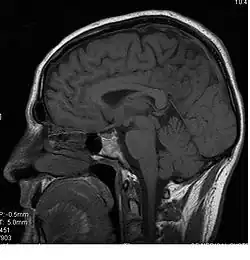

Le corps calleux (ou corpus callosum) est une commissure (moyen d'union entre deux parties) transversale du cerveau présente chez les mammifères placentaires[1]. C’est un faisceau d'axones (fibre nerveuse qui correspond au prolongement long, mince et cylindrique du corps cellulaire d'un neurone) interconnectant les deux hémisphères cérébraux. C'est la plus importante commissure du cerveau, car elle relie les huit lobes du cerveau entre eux (lobes frontaux, temporaux, pariétaux et occipitaux gauche et droit). Le corps calleux assure donc le transfert d'informations entre les deux hémisphères et ainsi leur coordination. Les autres commissures sont le fornix, le cingulum et la commissure blanche antérieure.

D’avant en arrière, on peut délimiter trois structures :

- le « genou » et le tiers antérieur du corps calleux (bec ou rostrum) sont ainsi formés par les fibres qui unissent les deux cortex (lobes) frontaux ;

- le tiers moyen (ou tronc) est formé par les fibres qui unissent les cortex pariétaux et temporaux ;

- la partie la plus postérieure, (bourrelet ou splenium), est formé par les fibres qui unissent les deux cortex occipitaux.

L'exposition prénatale à l'alcool affecte la construction du corps calleux[4]. Les lésions du corps calleux au cours de différents processus pathologiques (agénésie calleuse, patients split-brain, syndrome de Marchiafava-Bignami… ou plus exceptionnellement l'herpès néonatal congénital, c'est-à-dire acquis in utero[5]) auront pour conséquence une déconnexion cérébrale à l’origine d’une asynergie entre les deux hémisphères, connue sous le nom de syndrome de déconnexion calleuse. Les signes cliniques de ce syndrome vont donc largement dépendre de la localisation de la lésion sur le corps calleux. Par exemple, une lésion au niveau du splénium entraînera une anomie visuelle et une alexie unilatérale gauche (incapacité à dénommer des objets ou des lettres projetés dans le champ visuel gauche). Alors qu'une lésion au niveau du genou provoquera une apraxie idéomotrice gauche (incapacité à exécuter un geste symbolique tel qu'un salut militaire sur commande ou intentionnellement avec la main gauche). Ces exemples mettent bien en évidence toute l'importance du corps calleux et du transfert inter-hémisphérique. Le corps calleux ne joue pas un rôle important dans les pathologies neurodégénératives[6].